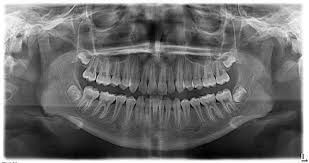

An OPG (Orthopantomagram) is a panoramic scanning dental X-ray of the upper and lower jaw. It is also sometimes called Orthopantomagraph or by the proprietary name Panorex. It shows a flattened two-dimensional view of a half-circle from ear to ear. Panoramic x-rays allow images of multiple angles to be taken to make up the composite panoramic image, where the maxilla (upper jaw) and mandible (lower jaw) are in the viewed area. The structures that are outside the viewed area are blurred. At some stage in your dental treatment, your dentist will likely take an OPG.